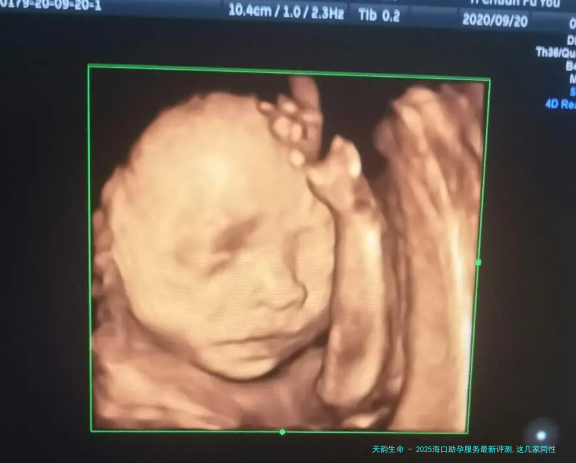

在椰风海韵、充满生机的海口,对于许多渴想构建完善家庭的特殊伴侣而言,当代人类辅助生殖技术如同一座希望的桥梁,让生命的奇观悄悄照进真实。2025年,这座城市的助孕服务在技术与人文关切上均取得了开创性发展,为不同需求的家庭打开了还要多科学且温暖的可能性。